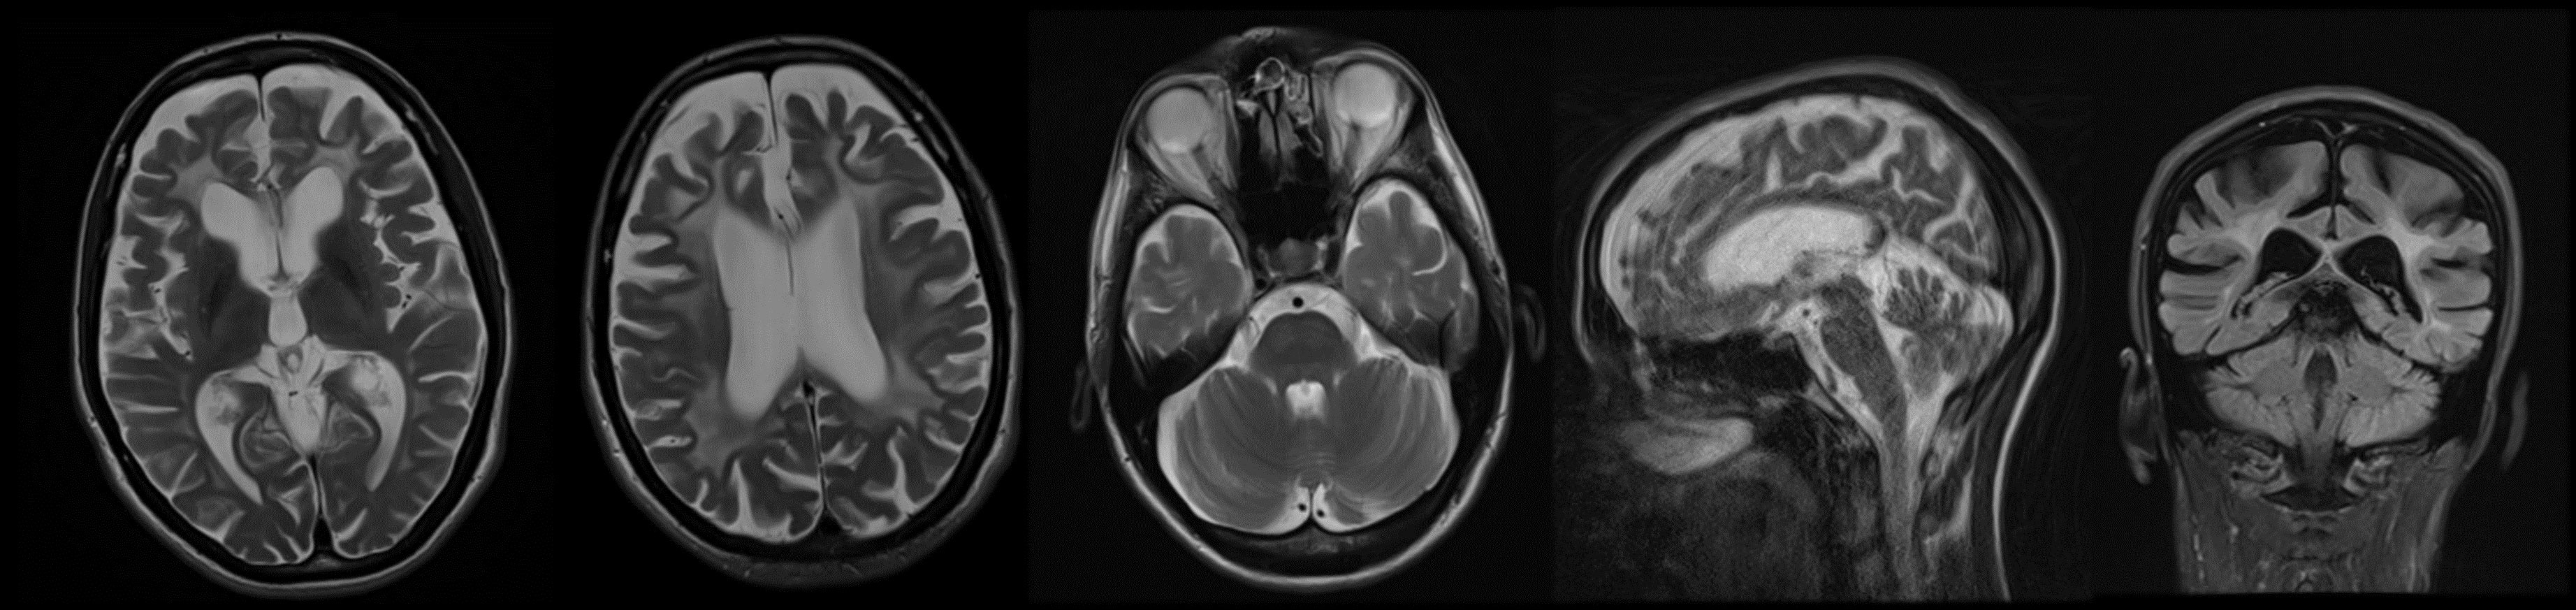

Figure 1

Bilateral symmetrical T2-weighted/FLAIR hyperintensities, together with global brain atrophy in patient carrying pathogenic variant in ARSA gene (Case 1).

Here we report a case of a young adult female who started developing behavioral changes at the age of 28 in the form of expressed jealousy, lying, and stealing things. Six years later her family members noticed involuntary movements of the head. She came to our clinic for the examination when she was 40 years of age and complained of weight loss, experienced instability while walking, and involuntary movement of her limbs, face, and trunk. Family history was negative for neurological disorders. The neurological examination showed generalized chorea with vocal tics, postural tremor of the hands, and voice. In addition to the above, she presented with dysarthria, wide gait, and mild dysmetria of the limbs (Video 1). The rest of the neurological examination was without impairment. Neuropsychological examination revealed dysexecutive syndrome. Laboratory analysis, immunoserology, tumor markers, and copper in urine were unremarkable. Autoimmune (antibodies against surface antigens and against intracellular antigens) and infectious causes (analysis for Borrelia burgdorferi, Human immunodeficiency virus and Treponema pallidum) were also excluded. As for the genetic testing, first, we excluded the presence of repeat expansions in HTT, TBP, ATN1, and c9orf72 gene. MRI results showed evidence of bilateral symmetrical hypointensities in T1-weighted, while hyperintensities in T2-weighted/FLAIR, together with global brain atrophy (Figure 1). Considering these findings we performed the analysis of the arylsulfatase activity in leukocytes and the activity was slightly reduced to 3.2 nmol/h/mL (reference range is 3.6–9.4 nmol/h/mL).

In this paper, we have shown that MLD may be presented in adulthood as a Huntington-like phenotype (HD-like phenotype), which has not been described in literature so far. In addition, we have provided a description of choreodystonic movements in a patient with an earlier onset of L2HGA confirming that chorea might be a significant part of the clinical manifestations in other hereditary leukodystrophies as well. There have already been descriptions of certain leukodystrophies that may be manifested as an HD-like phenotype, such as the rare Gordon Holmes syndrome which is characterized by hypogonadotropic hypogonadism, ataxia, cognitive decline, chorea, and signs of cerebral atrophy on the MRI of the brain [1, 10]. We showed that MLD has to be taken into consideration as differential diagnosis of HD-like phenotype and the hint could be MRI findings with symmetrical T2-weighted hyperintesities, which in adults starts in the rostral portion of the corpus callosum and frontal lobes [11].

Mutation in ARSA gene leads to decreased activity of arylsulfatase and consequently to demyelination and accumulation of cerebroside sulfate in the central and peripheral nervous system, and visceral organs [2, 12]. There are three phenotypes of MLD depending of age at onset. Late infantile type has the worst prognosis with regression in motor skills, walking difficulties, seizures, ataxia, hypotonia and optic atrophy. Juvenile-onset shows a slightly slower progression of the disorder, whereas in adulthood the disorder most frequently manifests itself in behavioral changes, dementia, and psychosis [5]. The dominant difficulties are attention disorders, processing speed, executive dysfunctions, which is all typical of disorders of frontal-subcortical circuits, so the adult forms are frequently being wrongly diagnosed as psychoses or frontotemporal dementia [13, 14]. Apart from the typical hyperintensity on MRI, predominantly in the frontal white matter, the changes in basal ganglia have also been described as a part of this disorder, which may explain the appearance of chorea and other involuntary movements in these patients. So far, one paper have stated that patients with MLD have the phenotype suggestive of dyskinetic movement disorder, while two more reported that patients might show chorea and dystonia, but without describing the actual cases [6, 8, 13].